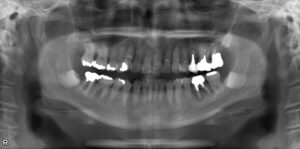

下顎大臼歯2本欠損症例

BEFORE AFTER 83歳男性/上2本欠損/インプラント埋込手術 【治療内容】 左下大臼歯の欠損補綴のご相談でご来…